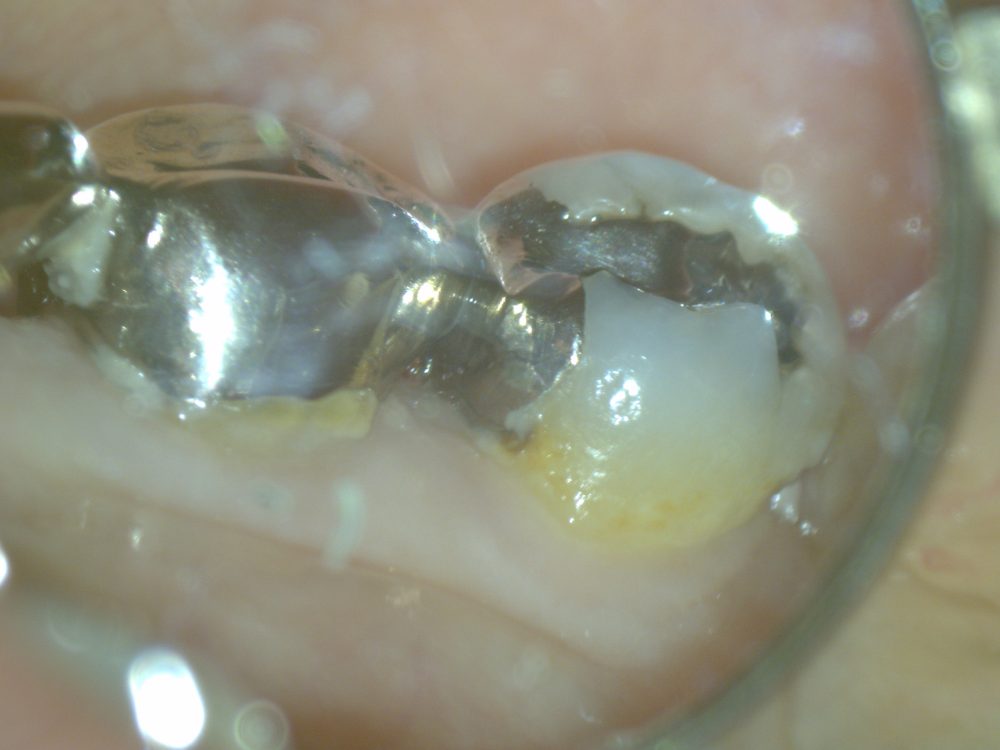

この写真をご覧ください。

金属の歯と歯ぐきの近くに沢山の汚れがついています。

歯と金属の際に汚れが溜まり虫歯になってしまいます。そして、金属の下で虫歯になってかぶせ物や詰め物を外して治療しないといけません。残せる歯は可能な限り残して、精確な治療で歯を少しでも守る必要があります。でも、一番大事なことは磨きの仕方を改めて清潔なお口を保つことです。